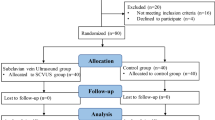

For the Part II study, we utilized PASS 15.0 software to estimate the sample size based on the observed incidence of PIH of 48.6% from our Part I study. Therefore, we assumed the significant difference α = 0.05, power of a test β = 0.8, and accounted for a 10% dropout rate. The sample size was determined to be 129. Patients were stratified into group L (SCVCI ≥ 45.4%) and group H (SCVCI < 45.4%) based on their pre-rehydration SCVCI values. Patients in group L received an intravenous bolus of colloid solution at a volume of 6 ml/kg over 20 min before induction [11]. Conversely, patients in group H did not receive additional fluid therapy before induction. dSCVmax, dSCVmin, SCVCI, SCVvariability, MAP and HR were recorded before and after rehydration. MAP and HR were assessed every minute until 10 min post-intubation, with the minimum value recorded. Furthermore, the 146 patients from Part I study were categorized into two groups: group L1 (SCVCI ≥ 45.4%) and group H1 (SCVCI < 45.4%). Subsequently, the incidence of PIH was compared among the four groups.

Part II: to explore the value of SCVCI combined with perioperative fluid therapy in preventing PIH in ASA I or II patients

In Part II study, 124 patients were categorized into two distinct groups based on their SCVCI values: group L (SCVCI ≥ 45.4%, n = 69) and group H (SCVCI < 45.4%, n = 55) (Fig. 2b). There were no significant differences in age, sex, height, BMI, ASA physical status, baseline MAP and HR between the L and H groups (P > 0.05). However, the albumin levels in group L were lower than those in group H (Table 4, P = 0.018).

Following perioperative fluid therapy, the SCVCI in group L significantly decreased post-administration compared to pre-administration levels (Table 5, P < 0.001). The incidence of PIH in group L and group H was 42.0% and 29.1%, respectively; however, no significant difference was observed between the two groups (P > 0.05).

The 146 patients included in Part I study were divided into group L1 (SCVCI ≥ 45.4%) and group H1 (SCVCI < 45.4%) based on preinduction SCVCI values to examine the influence of perioperative fluid therapy on preventing PIH. We found that the incidence of PIH in group H and group H1 was 29.1% and 21.7%, respectively, and there was no statistically significant difference in the incidence of PIH between the two groups. (P > 0.05). Conversely, patients in group L who received perioperative fluid therapy had a significantly lower incidence of PIH compared to group L1 (P < 0.001).